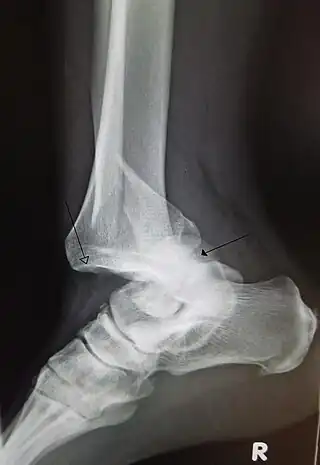

Dislocación traumática del tobillo con fractura del peroné distal. La flecha izquierda marca la ubicación de la tibia y la flecha derecha indica el astrágalo.

• Tobillo: una de las luxaciones más comunes, ya que a diferencia de otras, no necesita de golpes especialmente fuertes: las malas posturas, la inactividad física y el sobrepeso son causas que predisponen especialmente a esta clase de lesión.